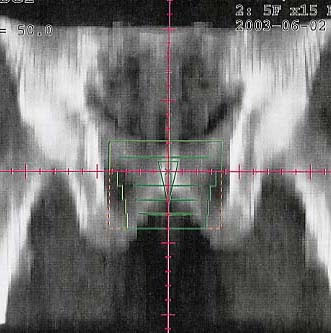

Prostatakarzinom: Bestrahlungsplan